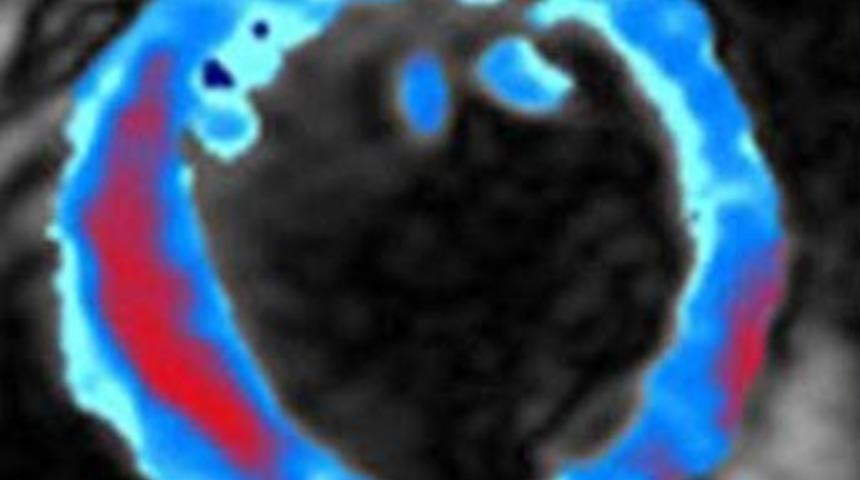

Doktorlar ilk kez bir kalp krizinin fotoğrafını çekmeyi başardılar.

Telegraph'ın haberine göre, bu hayati anın fotoğrafını yakalayan ekip bunun kalbin bir krize nasıl tepki gösterdiğini anlamayı sağlayacağını ve böylelikle de hastaların tedavisinin de gerçekleştirilebileceğini iddia ettiler.

Fotoğraflar, doktorların hastanın kalp krizi geçirmesi esnasında oluşan iç kanamayı görmelerini sağlıyor. Bu ekstra bilgi ile doktorlar müdahalelerini hastanın ihtiyacına göre ayarlayabilecekler.